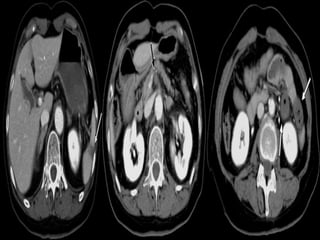

CT Scan Findings In Mesenteric

Ischemia

Specific CT signs

 Thromboembolism in the mesenteric

vessels

 Lack of bowel enhancement

 Circumferential bowel wall thickening:

-Target sign

 Intramural gas

 Portal vein gas

 Focal / diffuse bowel dilatation

 Bowel obstruction

 Increased attenuation of mesenteric fat (edema)

 Vascular engorgement

 Variable enhancement pattern

 Ascites

Nonspecific CT signs

Signs of bowel gangrene:

 Large amount of intraperitoneal fluid

 Gas in the mesenteric / portal vessels

 Thinned bowel wall with poor or absent

enhancement

CT Scan FindingsIn Mesenteric Ischemia Specific CT signs  Thromboembolism in the mesenteric vessels  Lack of bowel enhancement

 Circumferential bowelwall thickening: -Target sign  Intramural gas  Portal vein gas  Focal / diffuse bowel dilatation  Bowel obstruction  Increased attenuation of mesenteric fat (edema)  Vascular engorgement  Variable enhancement pattern  Ascites Nonspecific CT signs

Signs of bowelgangrene:  Large amount of intraperitoneal fluid  Gas in the mesenteric / portal vessels  Intramural gas  Thinned bowel wall with poor or absent enhancement